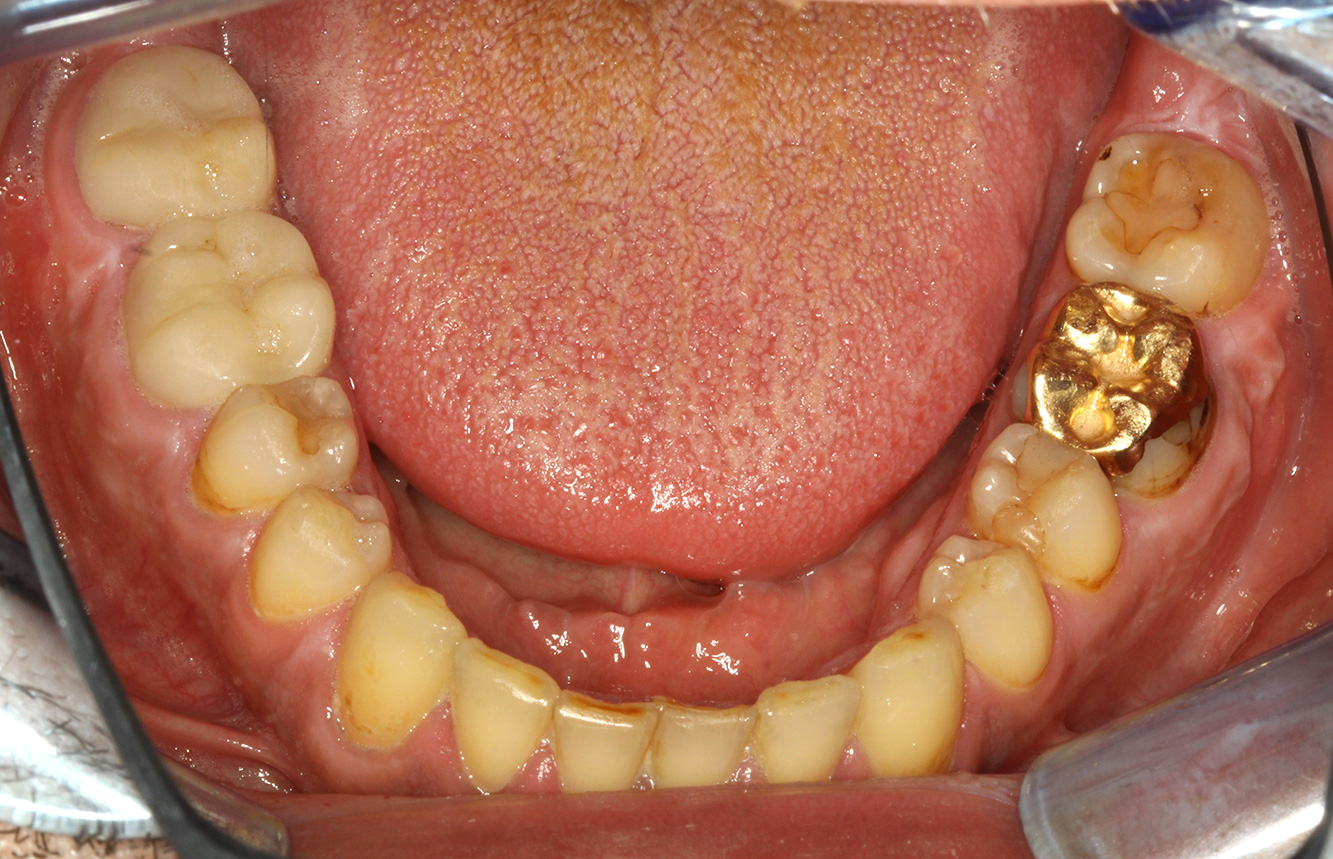

The patient is 39 years old and has previously undergone aortic valve replacement due to valve failure and endocarditis. ASS 100 is taken regularly as an anticoagulant. In terms of lifestyle, the patient’s diet is classified as caries-promoting due to the regular consumption of sugary foods and the fact that six to seven meals are consumed daily. The patient’s oral health indicates a moderate risk of caries, with active lesions. The risk of periodontitis is low, but gingivitis is present. The following recommendations are made for prophylactic treatment.

No specific instrument recommendations can be determined for the prophylaxis session. Targeted application of air and rotary polishing can be used to gently reduce plaque and stains on the restoration edges, and to reduce recolonization niches for cariogenic bacteria (19).

Fluoridation is recommended to further support the prevention of caries, and especially to prevent new formation around thethe restoration edges, and to seal the root surfaces. Both of these measures can reduce the teeth’s sensitivity to temperature.

Due to the active caries lesions and the associated risk of progression, a shortened recall interval of three to four months is recommended.